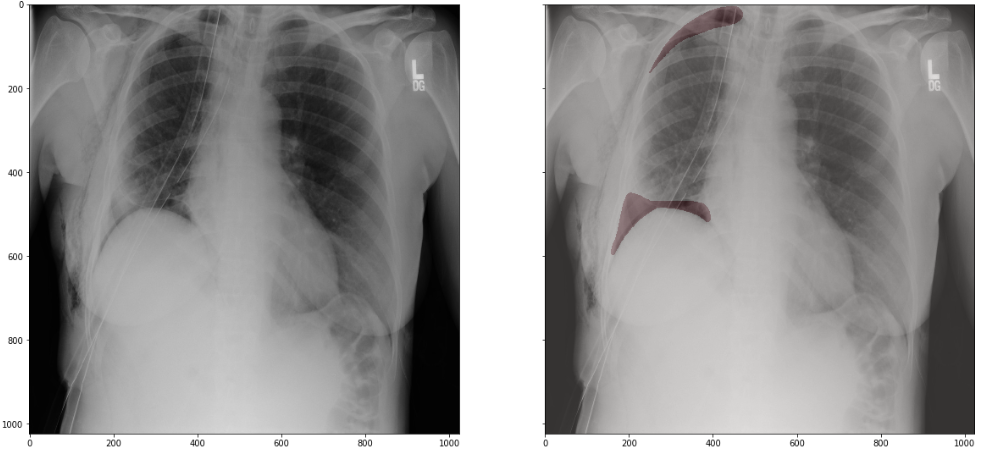

用一张图来表示作者的思路:

作者在训练模型时,采用5折交叉验证,并将模型训练分成了4个阶段(下文中分别表示成part0,part1,part2,part3),每个阶段都是上图中这样一个完整的过程,后一阶段直接在前一阶段的最优模型上fine-tuning.每一个阶段有不同的数据构成和模型参数。